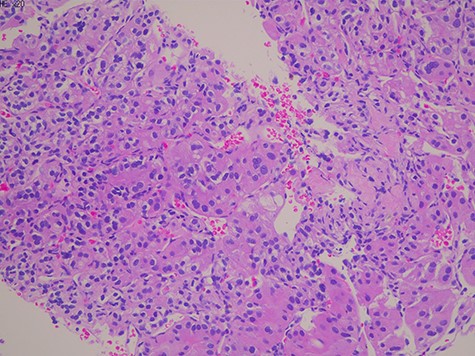

We found a clear cell renal cell cancer with a metastatic lung adenocarcinoma on CT-guided renal biopsy (Fig. 2). We were able to diagnose lung cancer from renal biopsy by immunohistochemical staining (Thyroid transcription factor 1 [TTF-1] and Napsin positive) without the primary lung tumor biopsy. The tumor was also positive for the following immunohistochemical markers: vimentin, cluster of differentiation 10 (CD10), heat shock protein 70, Glypcian-3, hepatocyte-specific antigen and paired-box gene 8.

Histology showed a proliferation of large nucleated atypical cells and eosinophilic cytoplasm. Some multinucleated cells with distinct nucleolus are scattered.